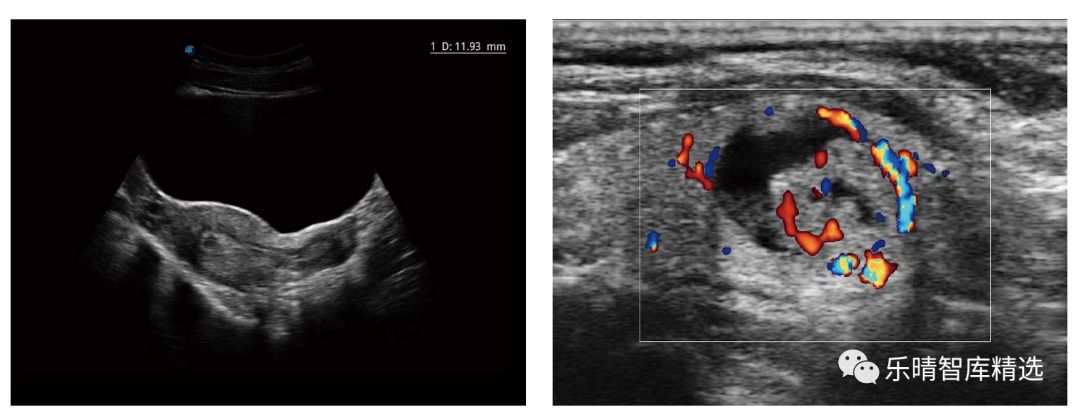

在分别收购了Zonare和Sonowise后,两家企业依靠自己强大的体系的力量,吸收优质的技术进行转化,在相隔几年的时间中都陆续推出了高端设备,图像优质,操作流简洁,而成为经典的爆款产品。

迈瑞的DC-8、R7等型号,开立的S50均已达到中高端水平,基本可以满足临床科室的基本需求,媲美进口品牌,在同档次的较量中,国产品牌功能更加丰富、产品性能更高、性价比更具优势,作为进口替代的基础要素——产品性能已经具备,中高端市场的进口替代正在全面铺开。